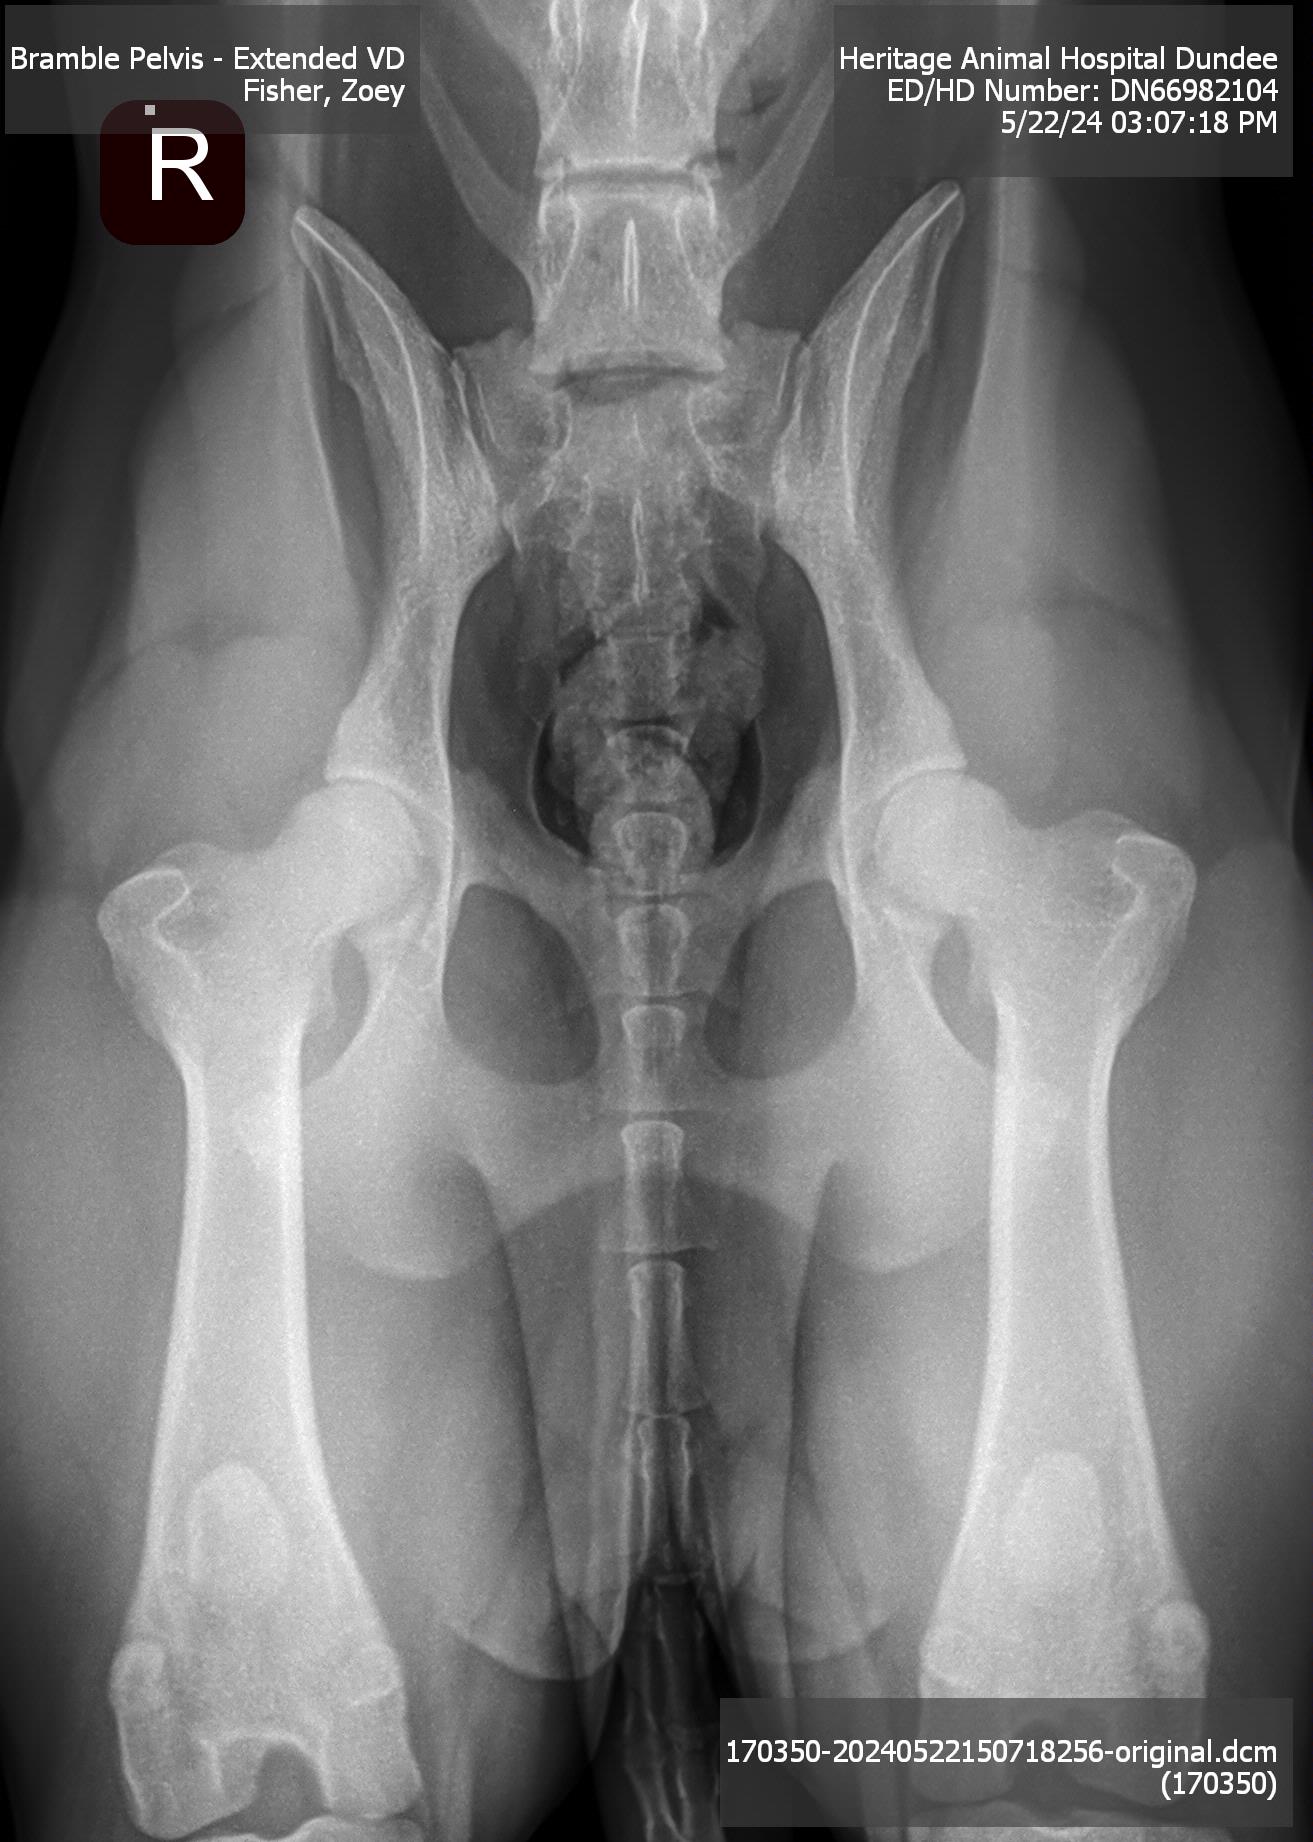

| Hips: |

Excellent |

Pedigree | OFA Database Entry | Hips | Left Elbow | Right Elbow